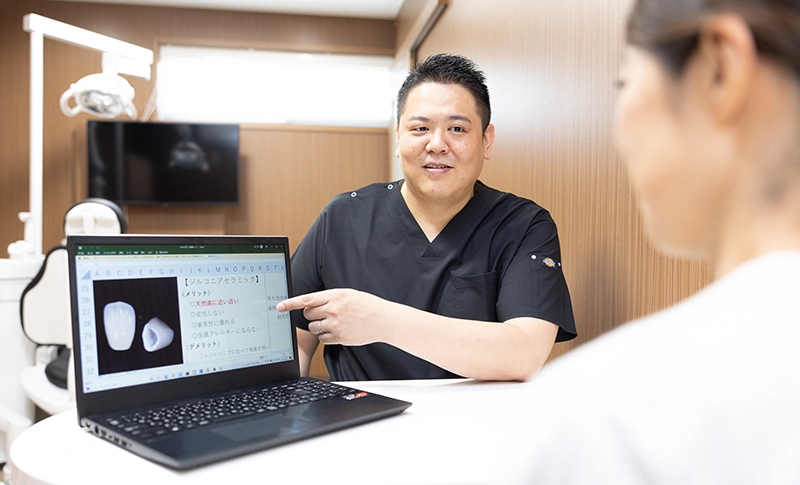

セラミックには複数の種類があります。代表的なものとして「オールセラミック」「e.maxセラミック(ガラスセラミック)」「ジルコニアセラミック」などがあり、素材ごとに強度・透明感・適している部位が異なります。

オールセラミックやe.maxは透明感が高く、前歯など目立つ部位に適しています。

一方、ジルコニアは非常に硬く耐久性に優れているため、強い噛む力がかかる奥歯に向いています。どの素材が最適かは、歯の位置や噛み合わせの状態によって変わります。